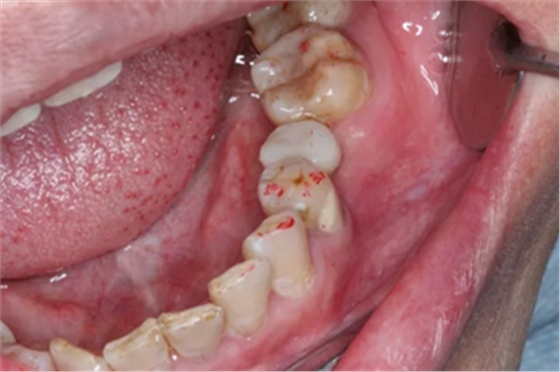

1.试戴临时基台,观看咬颌位置并且记录,将基台在口外进行调磨。

2.技师即刻对患者进行口内扫描,并将数据导入到设计软件中,在椅旁设计即刻修复体。

3.临时牙数据在椅旁切削机进行切削,十几分钟后便得到临时修复体。

4.医生将临时修复体与临时基台粘接后并且将其戴到患者口内。

5.临时修复体在患者口内就位后的状况。医生将咬颌纸放入患者口内将临时修复体进行观察调整。几乎没有经历调磨即可准确就位。